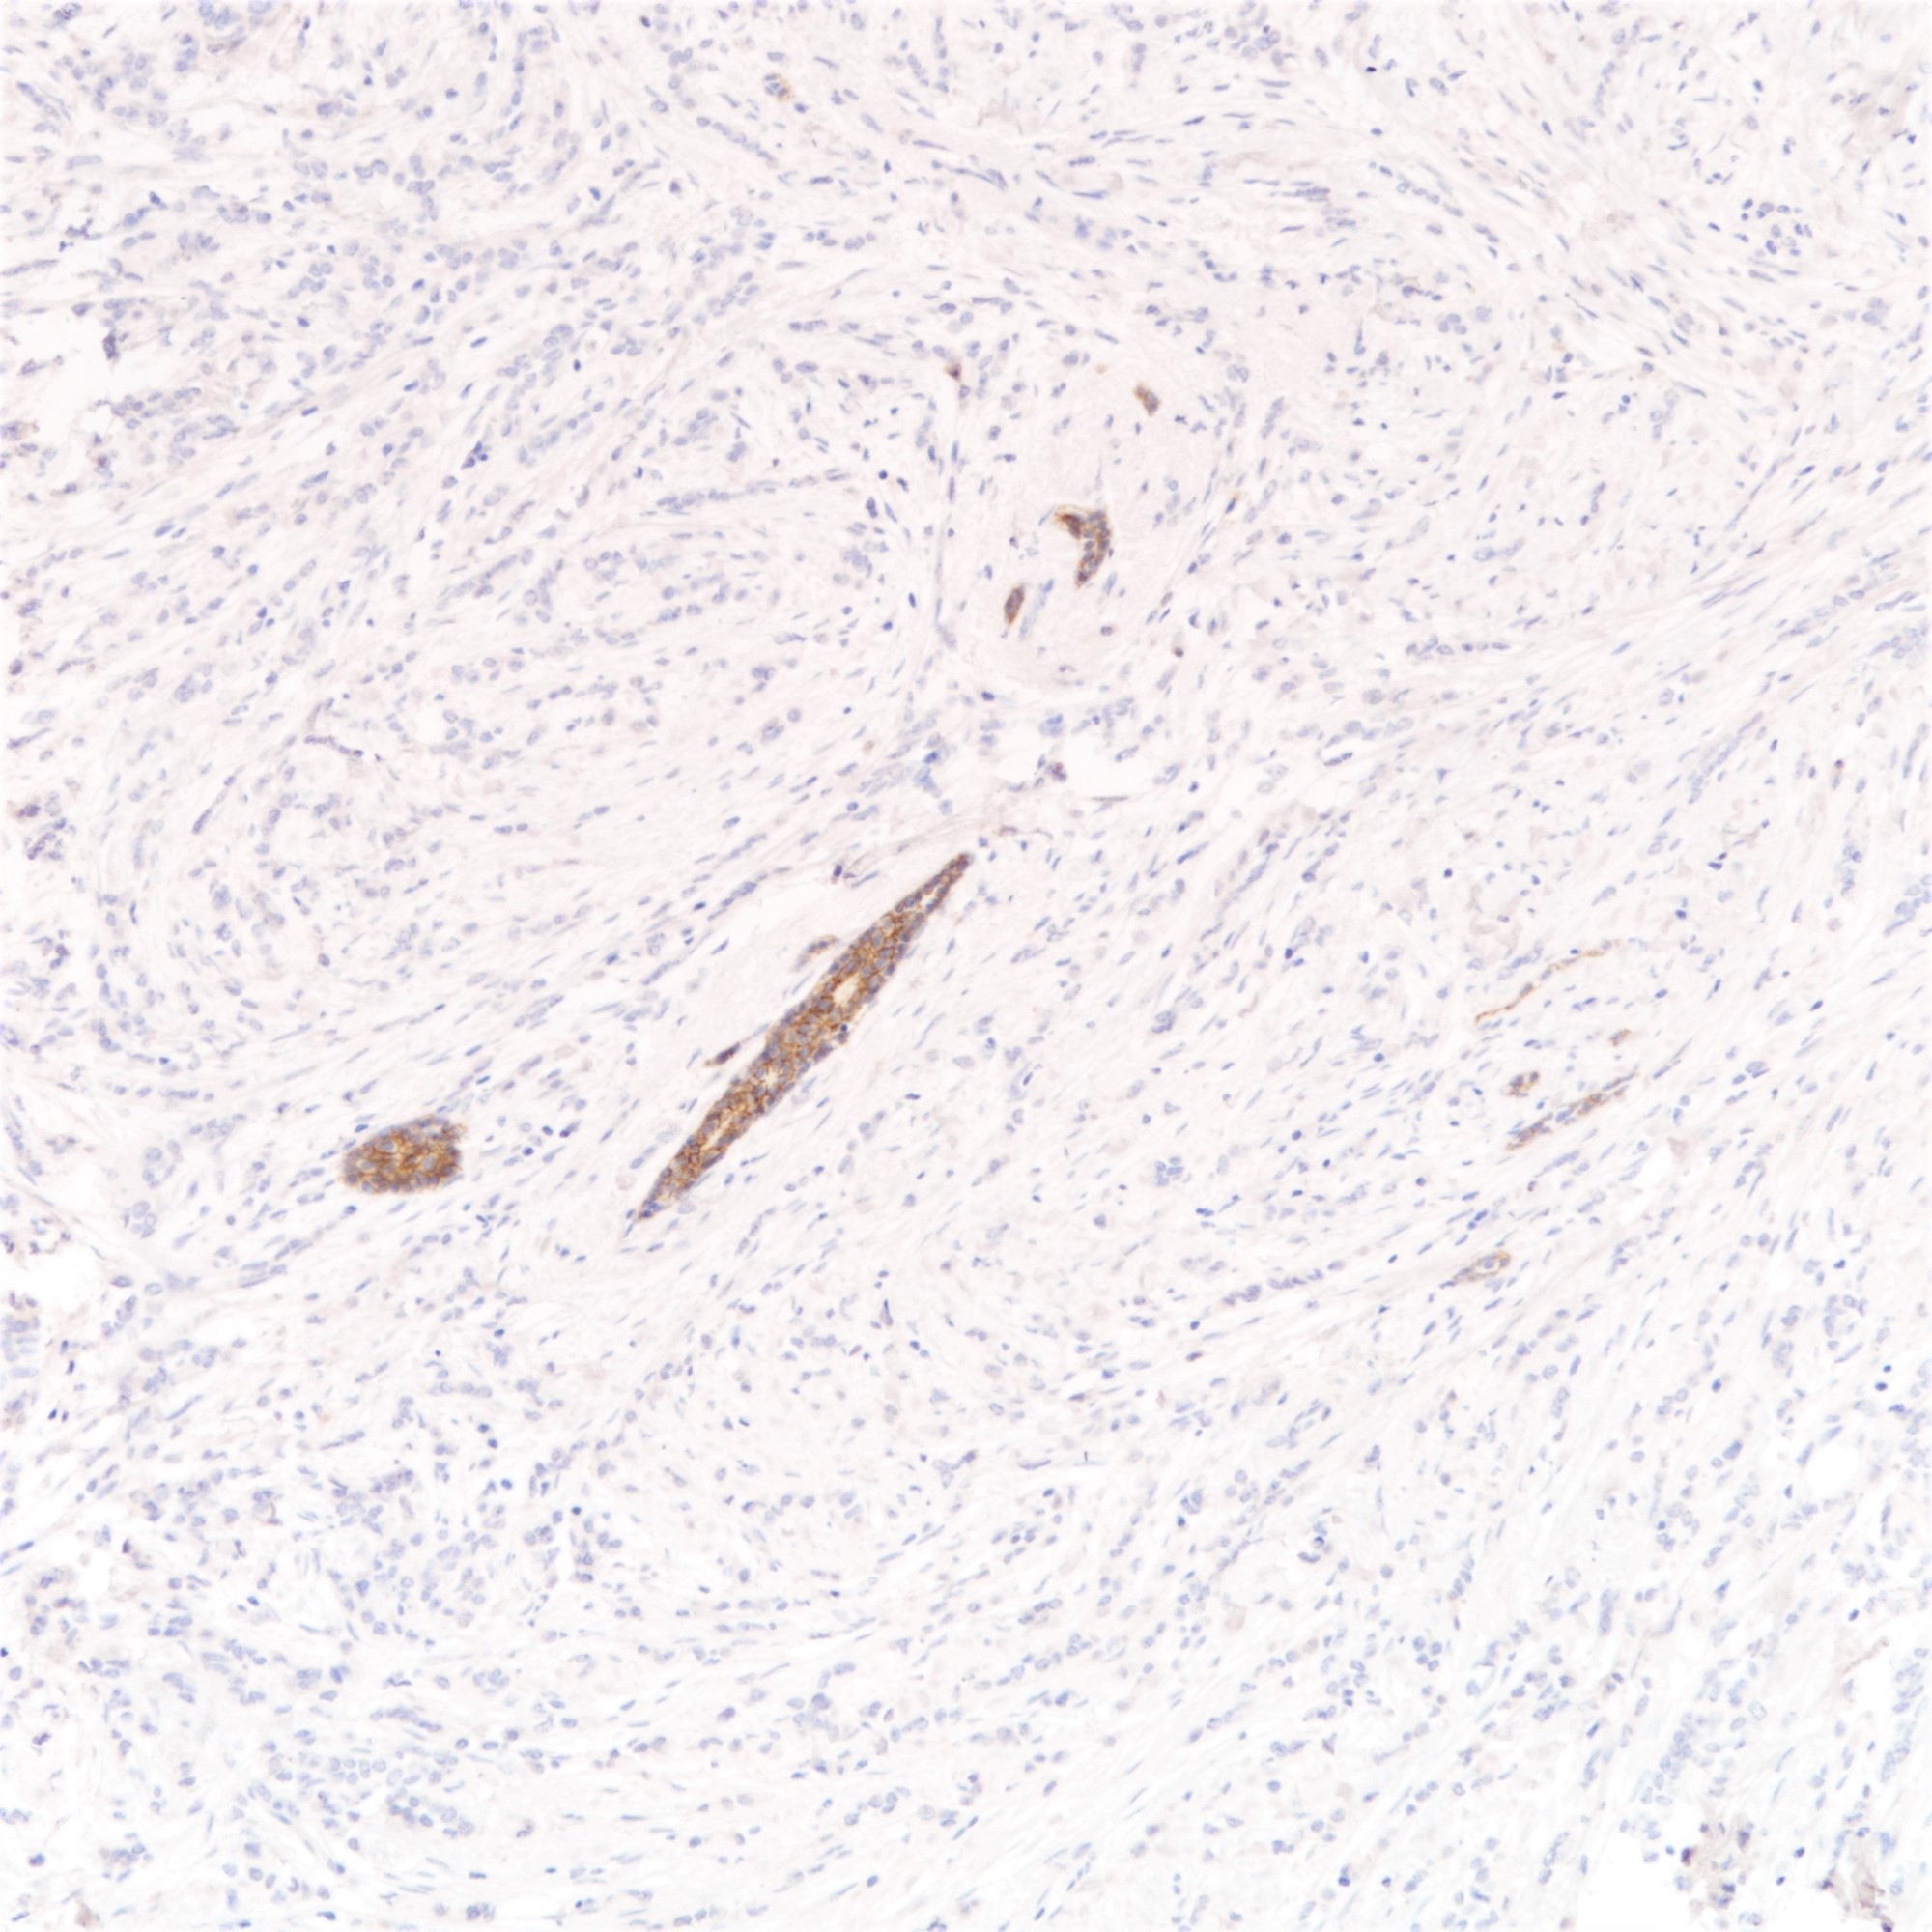

- Loss of E-cadherin expression on immunohistochemistry helpful but not required for diagnosis

- Majority of lobular carcinomas show loss of E-cadherin expression (Am J Surg Pathol 2010;34:1472)

- E-cadherin negative lobular carcinomas have a higher disease specific mortality than E-cadherin positive counterparts (Histopathology 2015;66:409)

Positive stains

Negative stains

- Abnormal expression of catenins

- E-cadherin (16%) (Am J Surg Pathol 2010;34:1472, Hum Pathol 2020;102:44)

- E-cadherin absence or reduction of membranous staining, useful but not necessary for diagnosis of lobular carcinoma

- Beta catenin (35% lost) (Eur J Surg Oncol 2001;27:31)

- E-cadherin (16%) (Am J Surg Pathol 2010;34:1472, Hum Pathol 2020;102:44)

- Comment: Sections show breast tissue with malignant cells in a diffuse and discohesive pattern, with some forming single files and small clusters. Targetoid pattern is noted. The tumor cells show mild nuclear pleomorphism with rare mitoses, corresponding to a Nottingham histological grade of I. No lymphovascular permeation is seen. The tumor measures ___cm in maximal dimension. The remaining breast tissue and nipple are unremarkable. All the resection margins are clear, with a minimal clearance of ___cm at the ___ margin. Immunohistochemical staining shows tumor cells are E-cadherin negative. The features are those of an infiltrating lobular carcinoma, classic type.